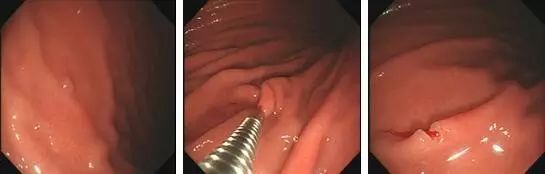

①高频电凝电切术:

为内镜治疗息肉中重要又常见的一种。这种方法利用高频电流将接触到圈套组织产生高热而被烧灼切断,完整快速地切除息肉并彻底止血。此方法不仅操作简便,病人无痛苦,费用低廉,并发症较少,而且能获得整个息肉的病理检查结果。

为什么说热活检钳胃肠息肉是怎么长出来的?有什么危害?如何预防和治疗?_https://www.jmylbn.com_新闻资讯_第8张1.发现息肉;2.热活检钳夹住息肉;3.钳除息肉